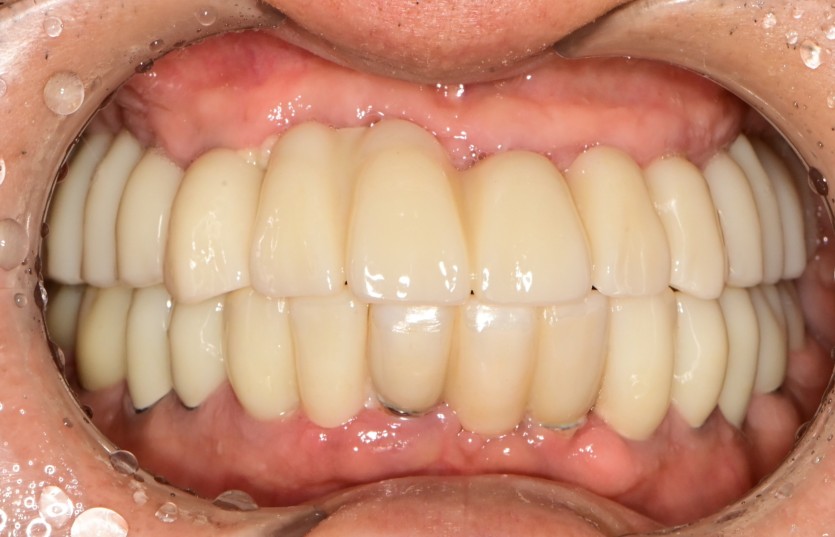

만 63세 전체 임플란트 증례(기존 임플란트 포함)

전체 임플란트 증례입니다.

(기존 임플란트 포함하여 교합 안정화)

16개의 임플란트로 완성하였습니다.